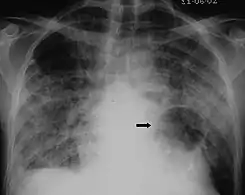

The diagnosis can be confirmed by the characteristic appearance of the chest X-ray and an arterial oxygen level (PaO2) that is strikingly lower than would be expected from symptoms. Gallium 67 scans are also useful in the diagnosis. They are abnormal in about 90% of cases and are often positive before the chest X-ray becomes abnormal. Chest X-ray typically shows widespread pulmonary infiltrates. CT scan may show pulmonary cysts (not to be confused with the cyst-forms of the pathogen).

Chest X-ray of increased opacification (whiteness) in the lower lungs.

These chest radiographs are of two patients. Both show ground glass opacities. The left X-ray shows a much more subtle ground-glass appearance while the right X-ray shows a much more gross ground-glass appearance mimicking pulmonary edema.[7]